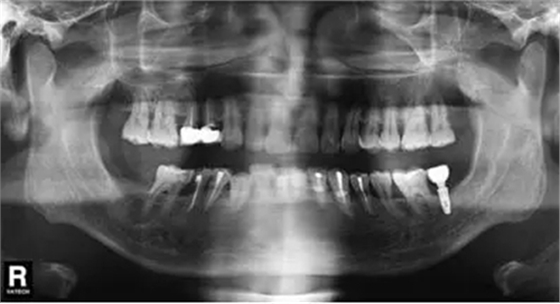

圖9 拔除47植入骨粉膠原塞曲面體層片

微創(chuàng)拔除47后,植入骨粉膠原塞(圖7~9);3個月后CBCT分析骨質(zhì);行47種植牙修復(fù)術(shù)。